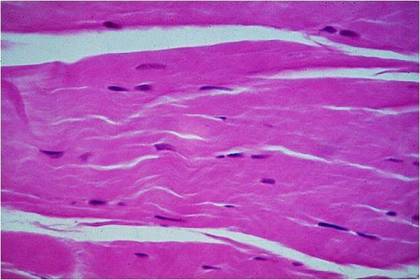

Tejido muscular: estriado